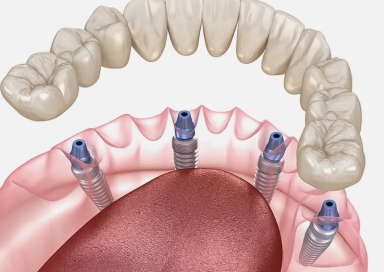

All-on-4(オールオンフォー)は、上顎・下顎に4本ずつのインプラントを埋入し、

その上に全ての人工歯を固定する画期的な治療法です。

従来のように10本以上のインプラントを必要とせず、

骨のある部分を活かして傾斜埋入することで、骨移植なしでも対応できるケースが多いのが特徴です。

All-on-4は、少ない本数のインプラントで多数の歯を支えることができる、

画期的な全顎再生治療です。

手術の負担が少なく、骨の量が足りない方でも対応できる可能性が高いため、

これまでインプラントを諦めていた方にも新しい希望をもたらします。